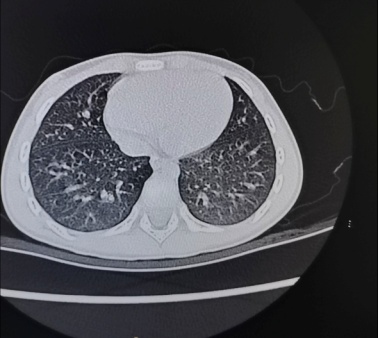

灌洗前肺CT 灌洗后肺CT 支气管镜下粘稠痰液

近日,北京儿童医院石景山诊疗中心(石景山医院儿科)为一名慕名而来的15岁重症肺炎患儿成功地完成了电子支气管镜灌洗介入治疗。患儿就诊时已发热、咳嗽1周左右,家长焦急万分,经过肺CT、病原学检查等相关检查后诊断为重症支原体肺炎。得知北京儿童医院石景山诊疗中心已开展电子支气管镜介入诊治技术后,当即来到儿科寻求进一步诊治。患儿入院后,立即实施灌洗术,术后当晚症状明显减轻,患儿感受舒适,术后第三天顺利出院,2周后复查肺CT显示原有病变完全吸收,患儿的父母亲自来到儿科病房对医护表示衷心地感谢,“孩子太幸运了,在家门口就享受到这么优质的医疗服务”。